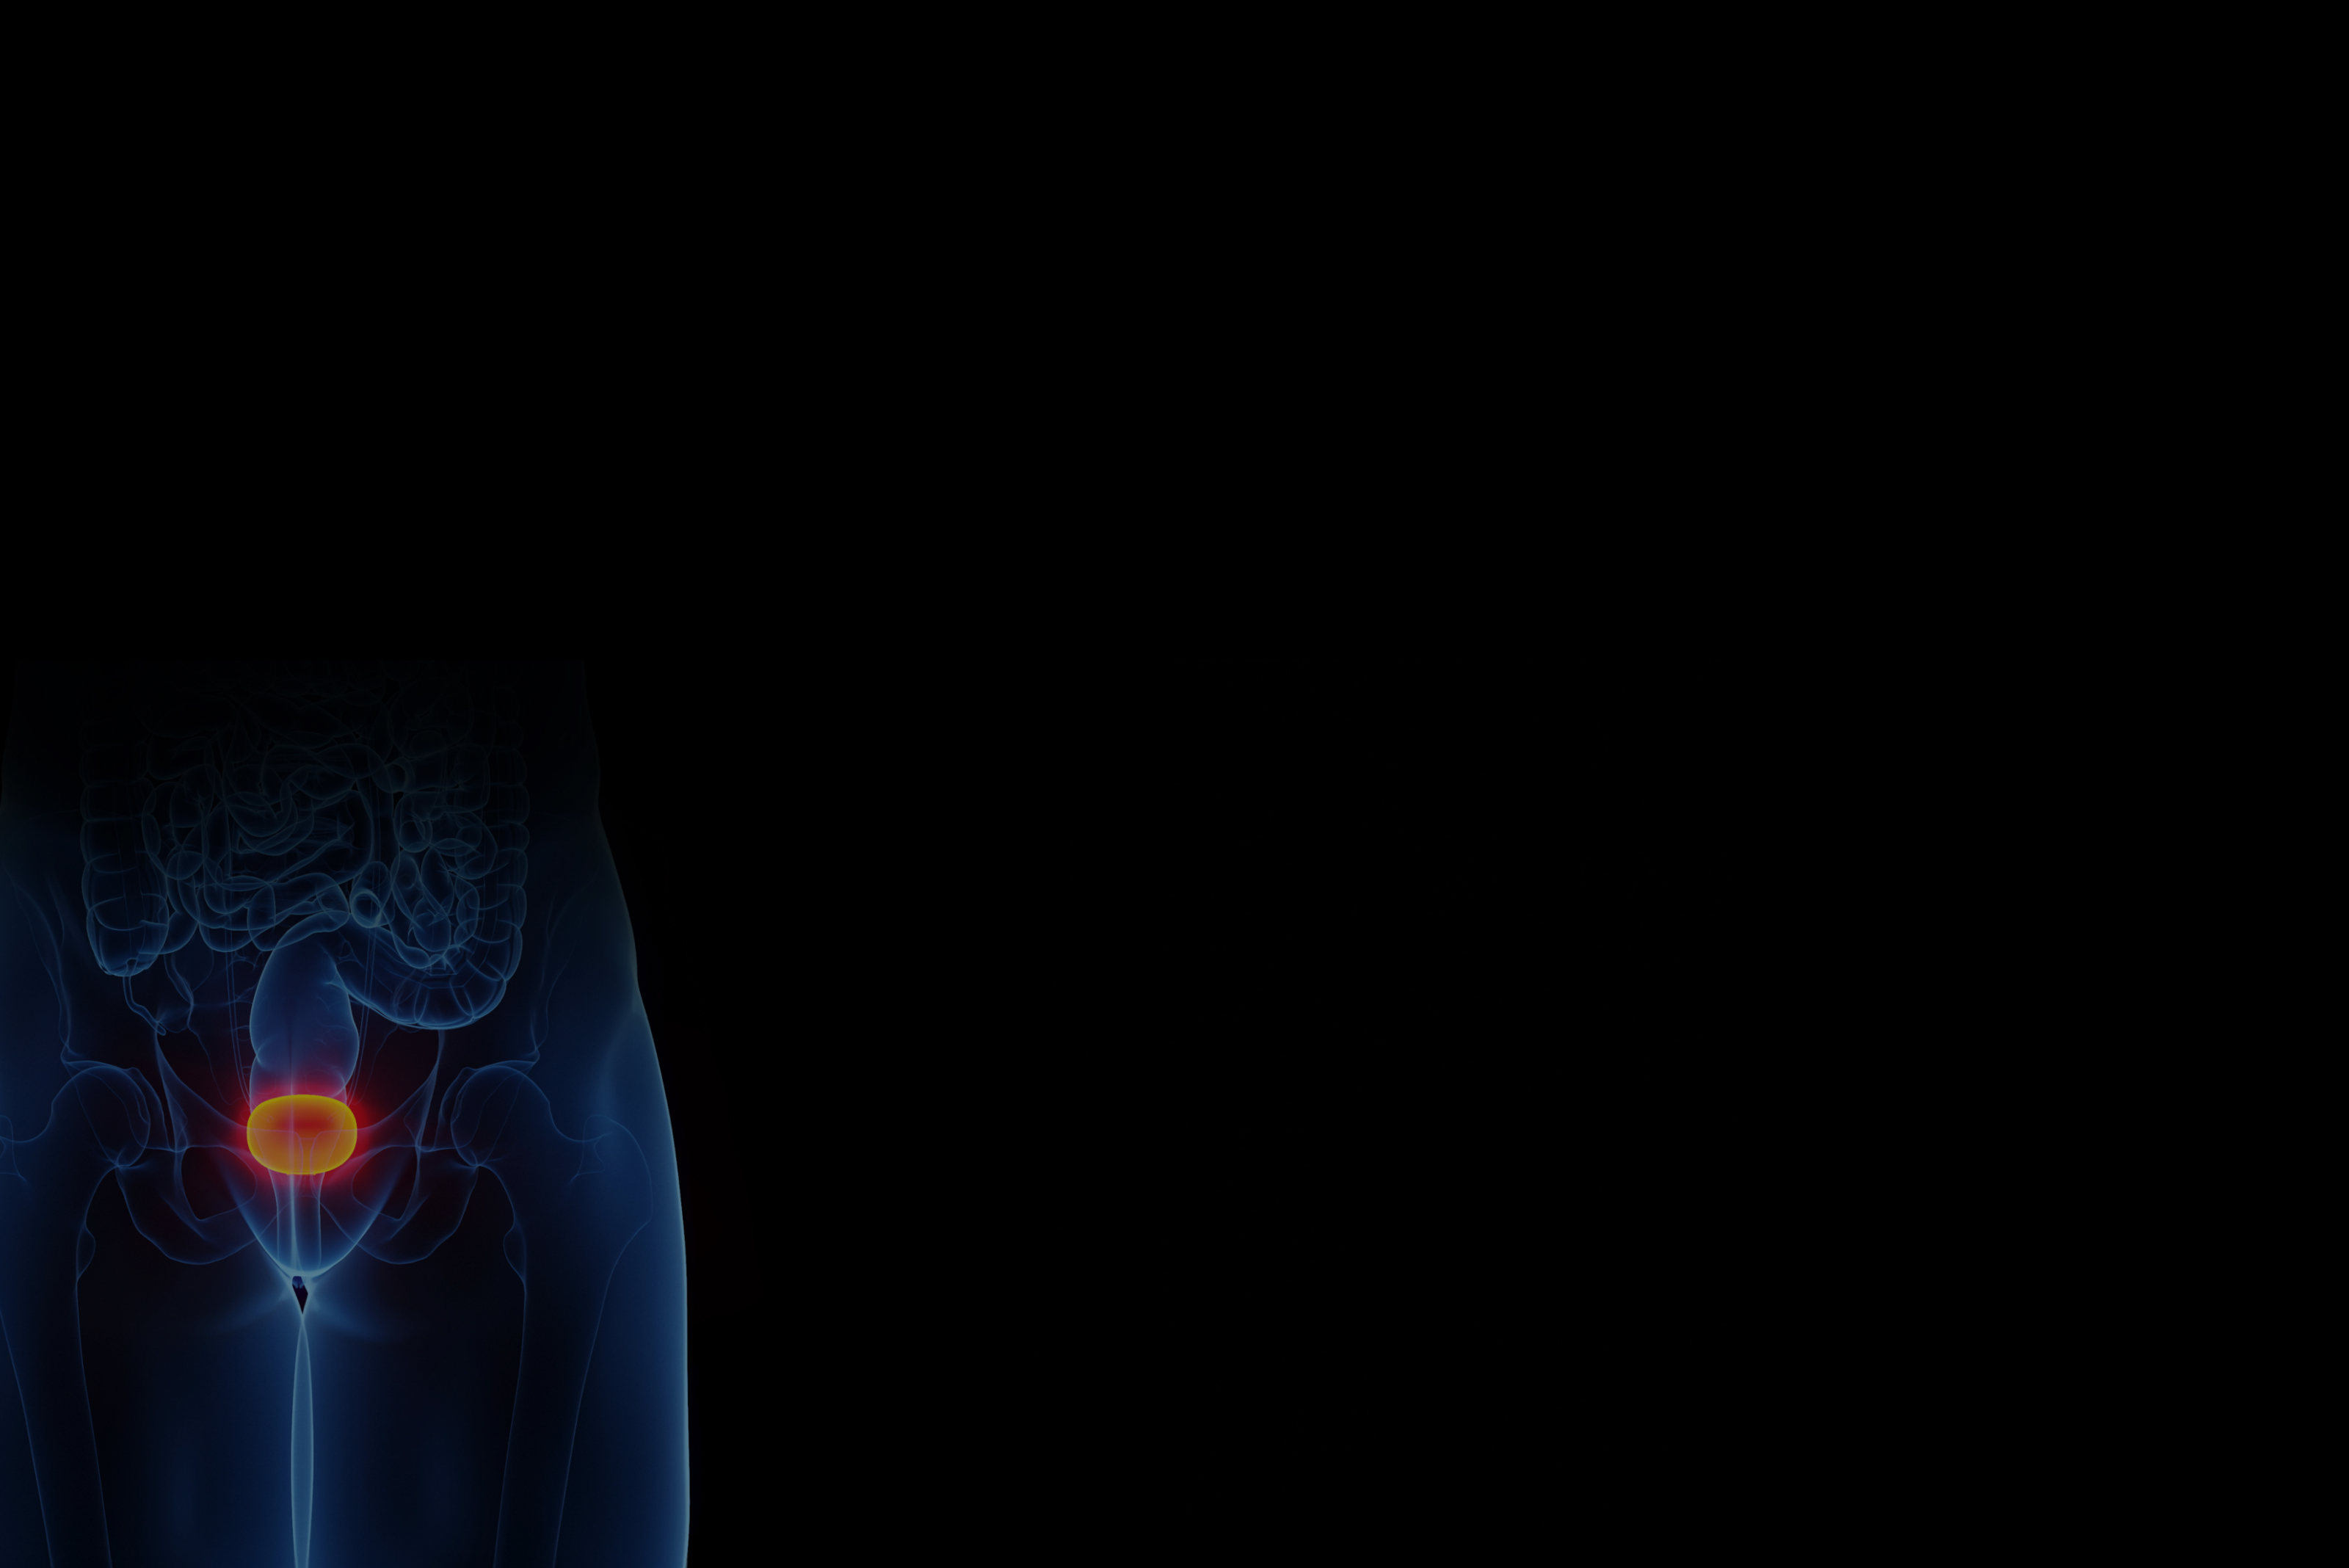

간질성 방광염,

골드만이 끝까지 책임집니다!

정밀 검사와 다각도 치료로 통증과 재발을 잡아 삶의 질을 높입니다.

골드만의 풍부한 경험과 노하우로 재발 걱정 없는 삶을 약속합니다.